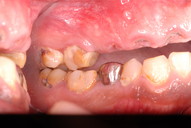

アメリカの矯正の実習、講演会に参加してきました。

10/31(

),11/1()

五反田のユーポートで、米国セントスイス大学、ハーバード大学で臨床教授も兼ねる

宮島先生という方の矯正の実習講演会に再参加してきました。

本年4月にも参加しましたが、時間がなく復習ができていなかったからです。

もともとは平成9年頃、矯正は埼玉県の歯科総合病院、渋谷病院で飯塚先生という方に習いましたが、知識を持ったとしてもすぐやる気もちなどなくそのうちあまりやらなくなっていたものでした。

ただ、最近、他の診療所で矯正を受けた人の虫歯や歯周病の酷さに驚く事が多いという事と、やはり普通の歯科治療でも矯正を使うと好ましい歯科治療ができるのですから、費用が少しかかるとしても説明してより良き治療を提案したいと思うようになりました